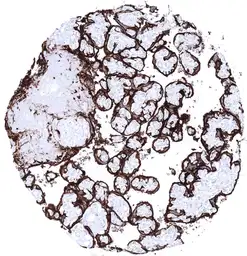

GTX04413 IHC-P Image

IHC-P analysis of human mature placenta (amnion and chorion) tissue using GTX04413 Placental Alkaline Phosphatase antibody [MSVA-350R] HistoMAX™.

Membranous Placental Alkaline Phosphatase immunostaining is strong in chorion cells.